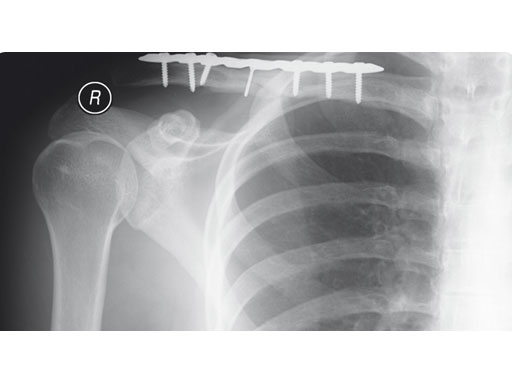

A 22-year-old man sustained an open clavicle fracture after a motorcycle injury.

Fig 1ab Preoperative x-rays.